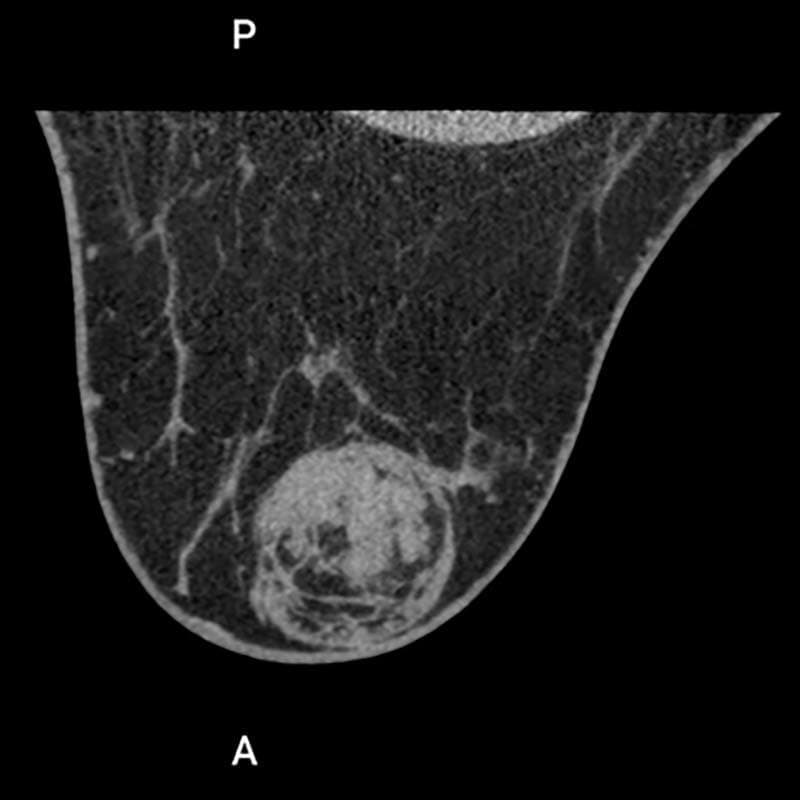

多発性乳がん

患者背景

• 70~79歳の女性で、右乳房に触知可能な腫瘤を認める。

• 過去のマンモグラフィでは単一の腫瘤のみが描出されていた。

• 超音波検査では、病変は円形かつ境界明瞭で、嚢胞性と固形成分を伴っていた。さらに、滑らかで不規則な辺縁を有する複数の低エコー性病変が検出された。

多発性乳がんの疑いを確認するため、乳腺CT検査を実施した。

画像詳細

• 造影前:円形の腫瘤性病変で、中心部に低吸収(壊死/液体)領域を認める。画像所見は複数の病変を疑わせる。

• 造影後:触知可能な腫瘤は造影剤を不均一に増強します。乳房の複数の象限に、不規則な縁と滑らかな縁を有する複数の造影増強腫瘤が明示されています。

評価:BI-RADS 5

画像提供:エヴリン・ヴェンケル医学博士(エルランゲン大学病院)